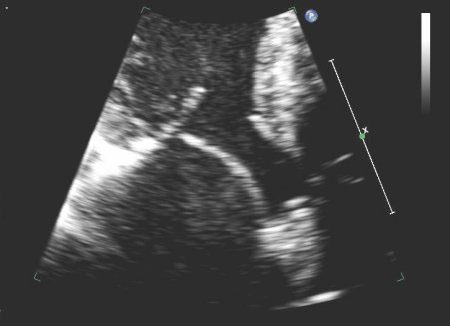

May result from abnormal elasticity with redundancy and enlargement of various portions of the mitral valvular apparatus, including the mitral annulus, chordae tendineae, and leaflets.[5][6][7][Figure caption and citation for the preceding image starts]: Posterior mitral valve prolapse on M-mode echoFrom the collection of Samir Kapadia and Mehdi H. Shishehbor [Citation ends].

[Figure caption and citation for the preceding image starts]: Parasternal long-axis view showing posterior mitral leaflet prolapseFrom the collection of Samir Kapadia and Mehdi H. Shishehbor [Citation ends].